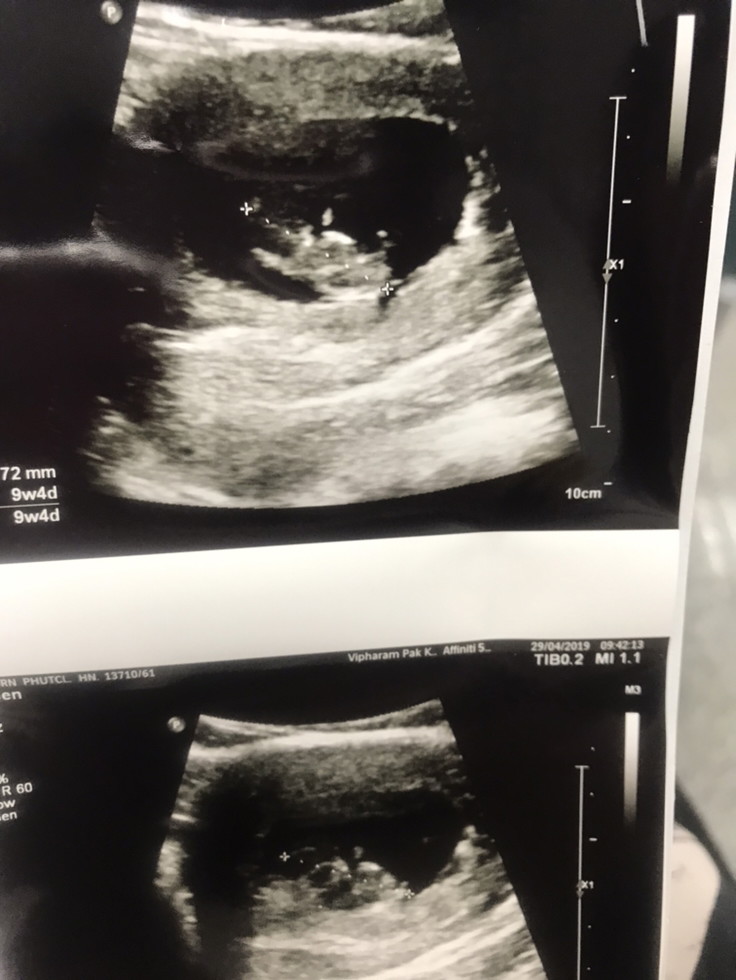

9สัปดาห์ค่ะ ตอนนี้16สัปดาห์แล้ว 🥰